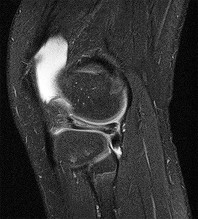

Question 4:

A 22-year-old female soccer player undergoes primary anterior cruciate ligament (ACL) reconstruction using a bone-patellar tendon-bone autograft. Postoperatively, she experiences loss of terminal extension and anterior knee pain. An MRI indicates graft impingement against the intercondylar roof. Which of the following technical errors during tunnel preparation is the most common cause of this specific impingement pattern?